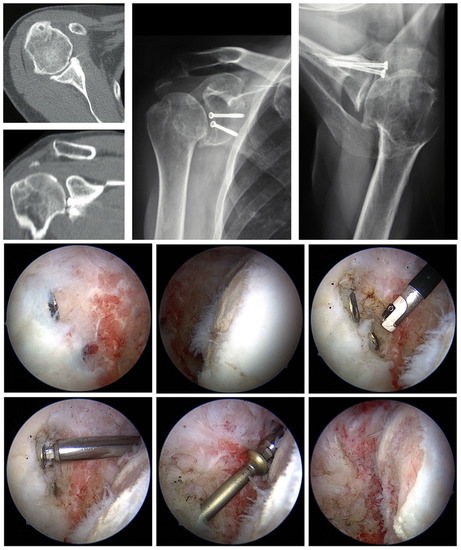

6.2. Removal of Foreign Material

6.3. Arthroscopic Debridement and Arthrolysis